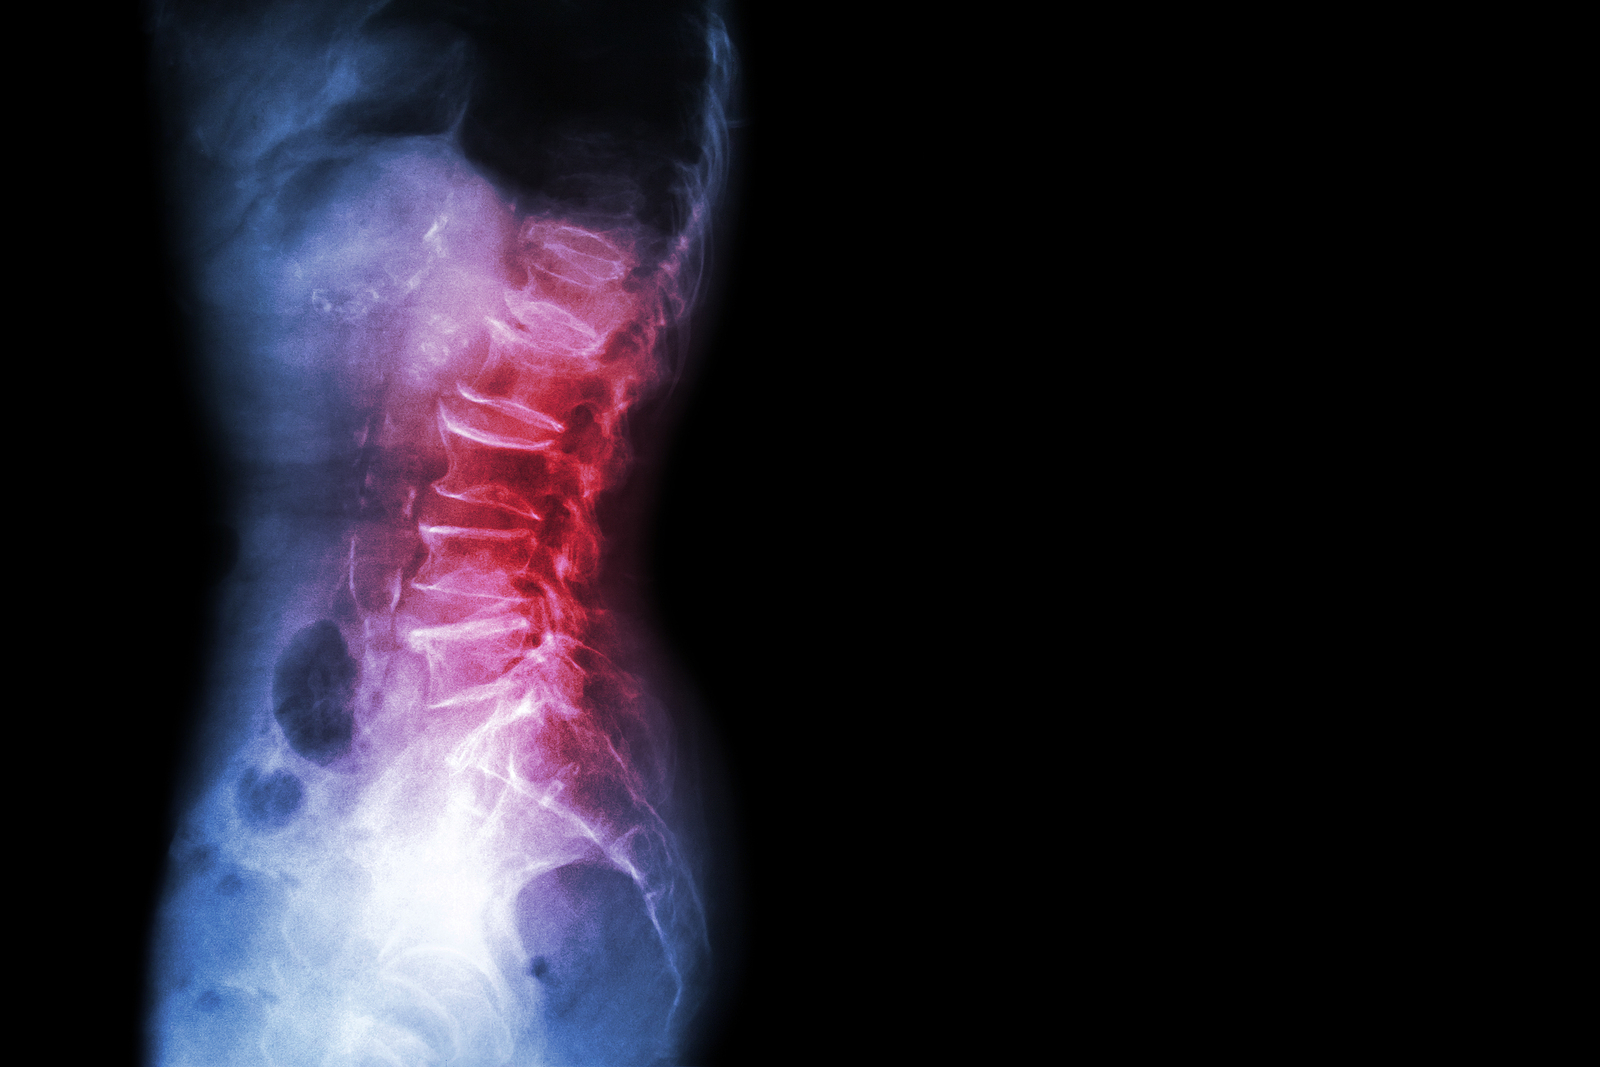

Anatomy

What Makes Up the Lumbar Spine?

The human spine is made up of 24 spinal bones, called vertebrae, as well as the sacrum and the coccyx. The sacrum is a triangular bone near the bottom of the spine and the coccyx is more commonly known as the tailbone.

Vertebrae are stacked on top of one another to create the spinal column. The spinal column gives the body its form and helps sustain an upright position.

The lumbar spine—where pain is often experienced—is made up of five vertebrae positioned near the bottom of the spinal column. Doctors often refer to these vertebrae as levels L1, L2, L3, L4 and L5. The ‘L’ refers to ‘lumbar’. The lowest vertebra, L5, is connected to the top of the sacrum—a triangular bone at the base of the spine that is located between the two pelvic bones. Some people are born with an extra or sixth lumbar vertebra called L6. Having an extra vertebra doesn't usually cause physical problems.

X-rays

X-rays are usually the first test ordered before any of the more specialized tests are completed. X-rays use electromagnetic radiation to show problems with bones and can also reveal problems such as fractures, infections, or bone tumors. X-rays of the spine can give your doctor information about bone alignment and can demonstrate how much degeneration has occurred in the spine. Both alignment and degeneration can affect the amount of space in the neural foramina and between the discs, which subsequently impacts the nerves in the area. This is important information your health care professional can use to establish a treatment plan.